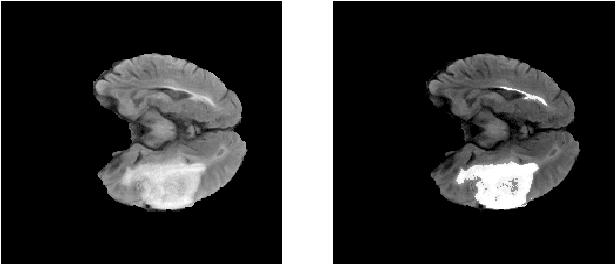

Abstract:Glioma is a common type of brain tumor, and accurate detection of it plays a vital role in the diagnosis and treatment process. Despite advances in medical image analyzing, accurate tumor segmentation in brain magnetic resonance (MR) images remains a challenge due to variations in tumor texture, position, and shape. In this paper, we propose a fast, automated method, with light computational complexity, to find the smallest bounding box around the tumor region. This region-of-interest can be used as a preprocessing step in training networks for subregion tumor segmentation. By adopting the outputs of this algorithm, redundant information is removed; hence the network can focus on learning notable features related to subregions' classes. The proposed method has six main stages, in which the brain segmentation is the most vital step. Expectation-maximization (EM) and K-means algorithms are used for brain segmentation. The proposed method is evaluated on the BraTS 2015 dataset, and the average gained DICE score is 0.73, which is an acceptable result for this application.